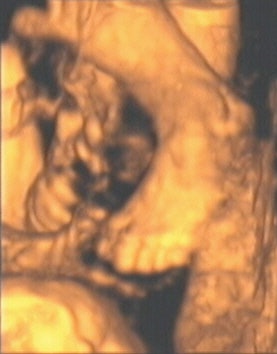

![]() |

| Figure 9, a 3-D ultrasound image of a fetal foot at 28 weeks gestation. Image courtesy of Stefano Ciatti, M.D. |